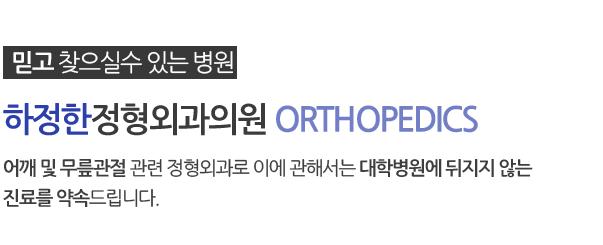

팔꿈치 인공관절